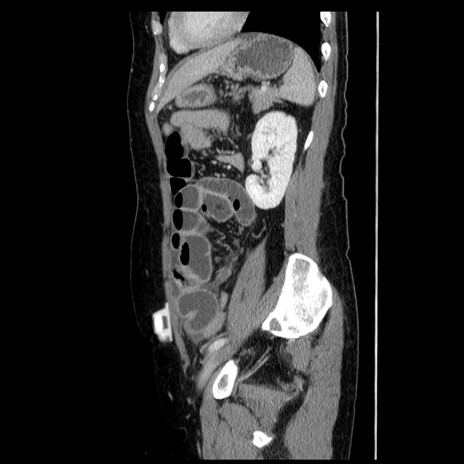

症例6(矢状断像)

【症例】50歳代女性

【主訴】下腹部痛

【既往歴】卵巣癌術後(8年前に当院で卵巣摘出)